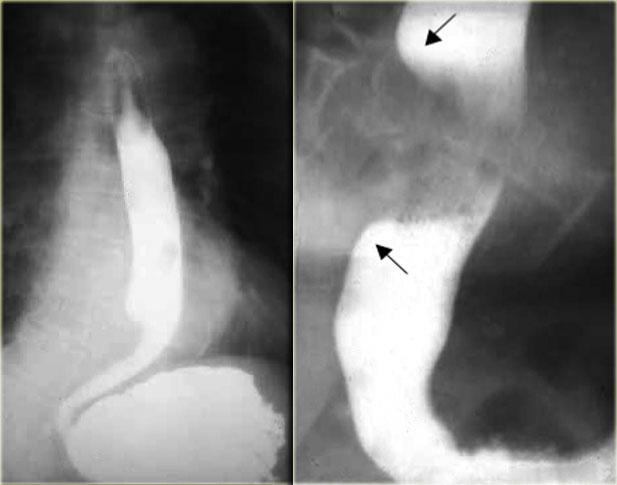

Hình ảnh ngoài cùng bên trái cho thấy vị trí hẹp (mũi tên) với các nếp niêm mạc không đều tại vùng hẹp trên hình ảnh đối quang không khí.

Bệnh nhân này được chẩn đoán thực quản Barrett.

Hẹp và loét thực quản đoạn giữa cần nghi ngờ thực quản Barrett.

Hai hình ảnh bên phải cho thấy thực quản Barrett với vùng hẹp không đều do ung thư biểu mô tuyến.